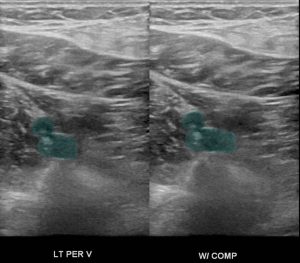

The diagnosis of calf vein thrombosis is established with duplex ultrasound utilizing the same principles that are used in proximal deep vein thrombi. A thrombus is diagnosed if there is lack of compression and/or lack of augmentation of flow. Also if there is no flow in the vein it may suggest a thrombosis. Some vascular laboratories do not perform calf ultrasound routinely, while others do. It is a matter of debate whether or not calf duplex ultrasonography is an accurate method to detect thrombi, however it has been published that a high standard laboratory can establish a low rate of clinically significant missed diagnoses.